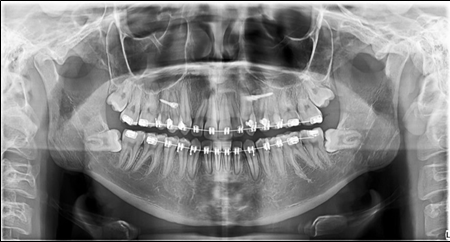

Before the finishing stage, a panoramic x-ray was taken. The third molars were removed .(Figure 6)

Figure 6.Panoramic X-ray before the removal of the third molars.